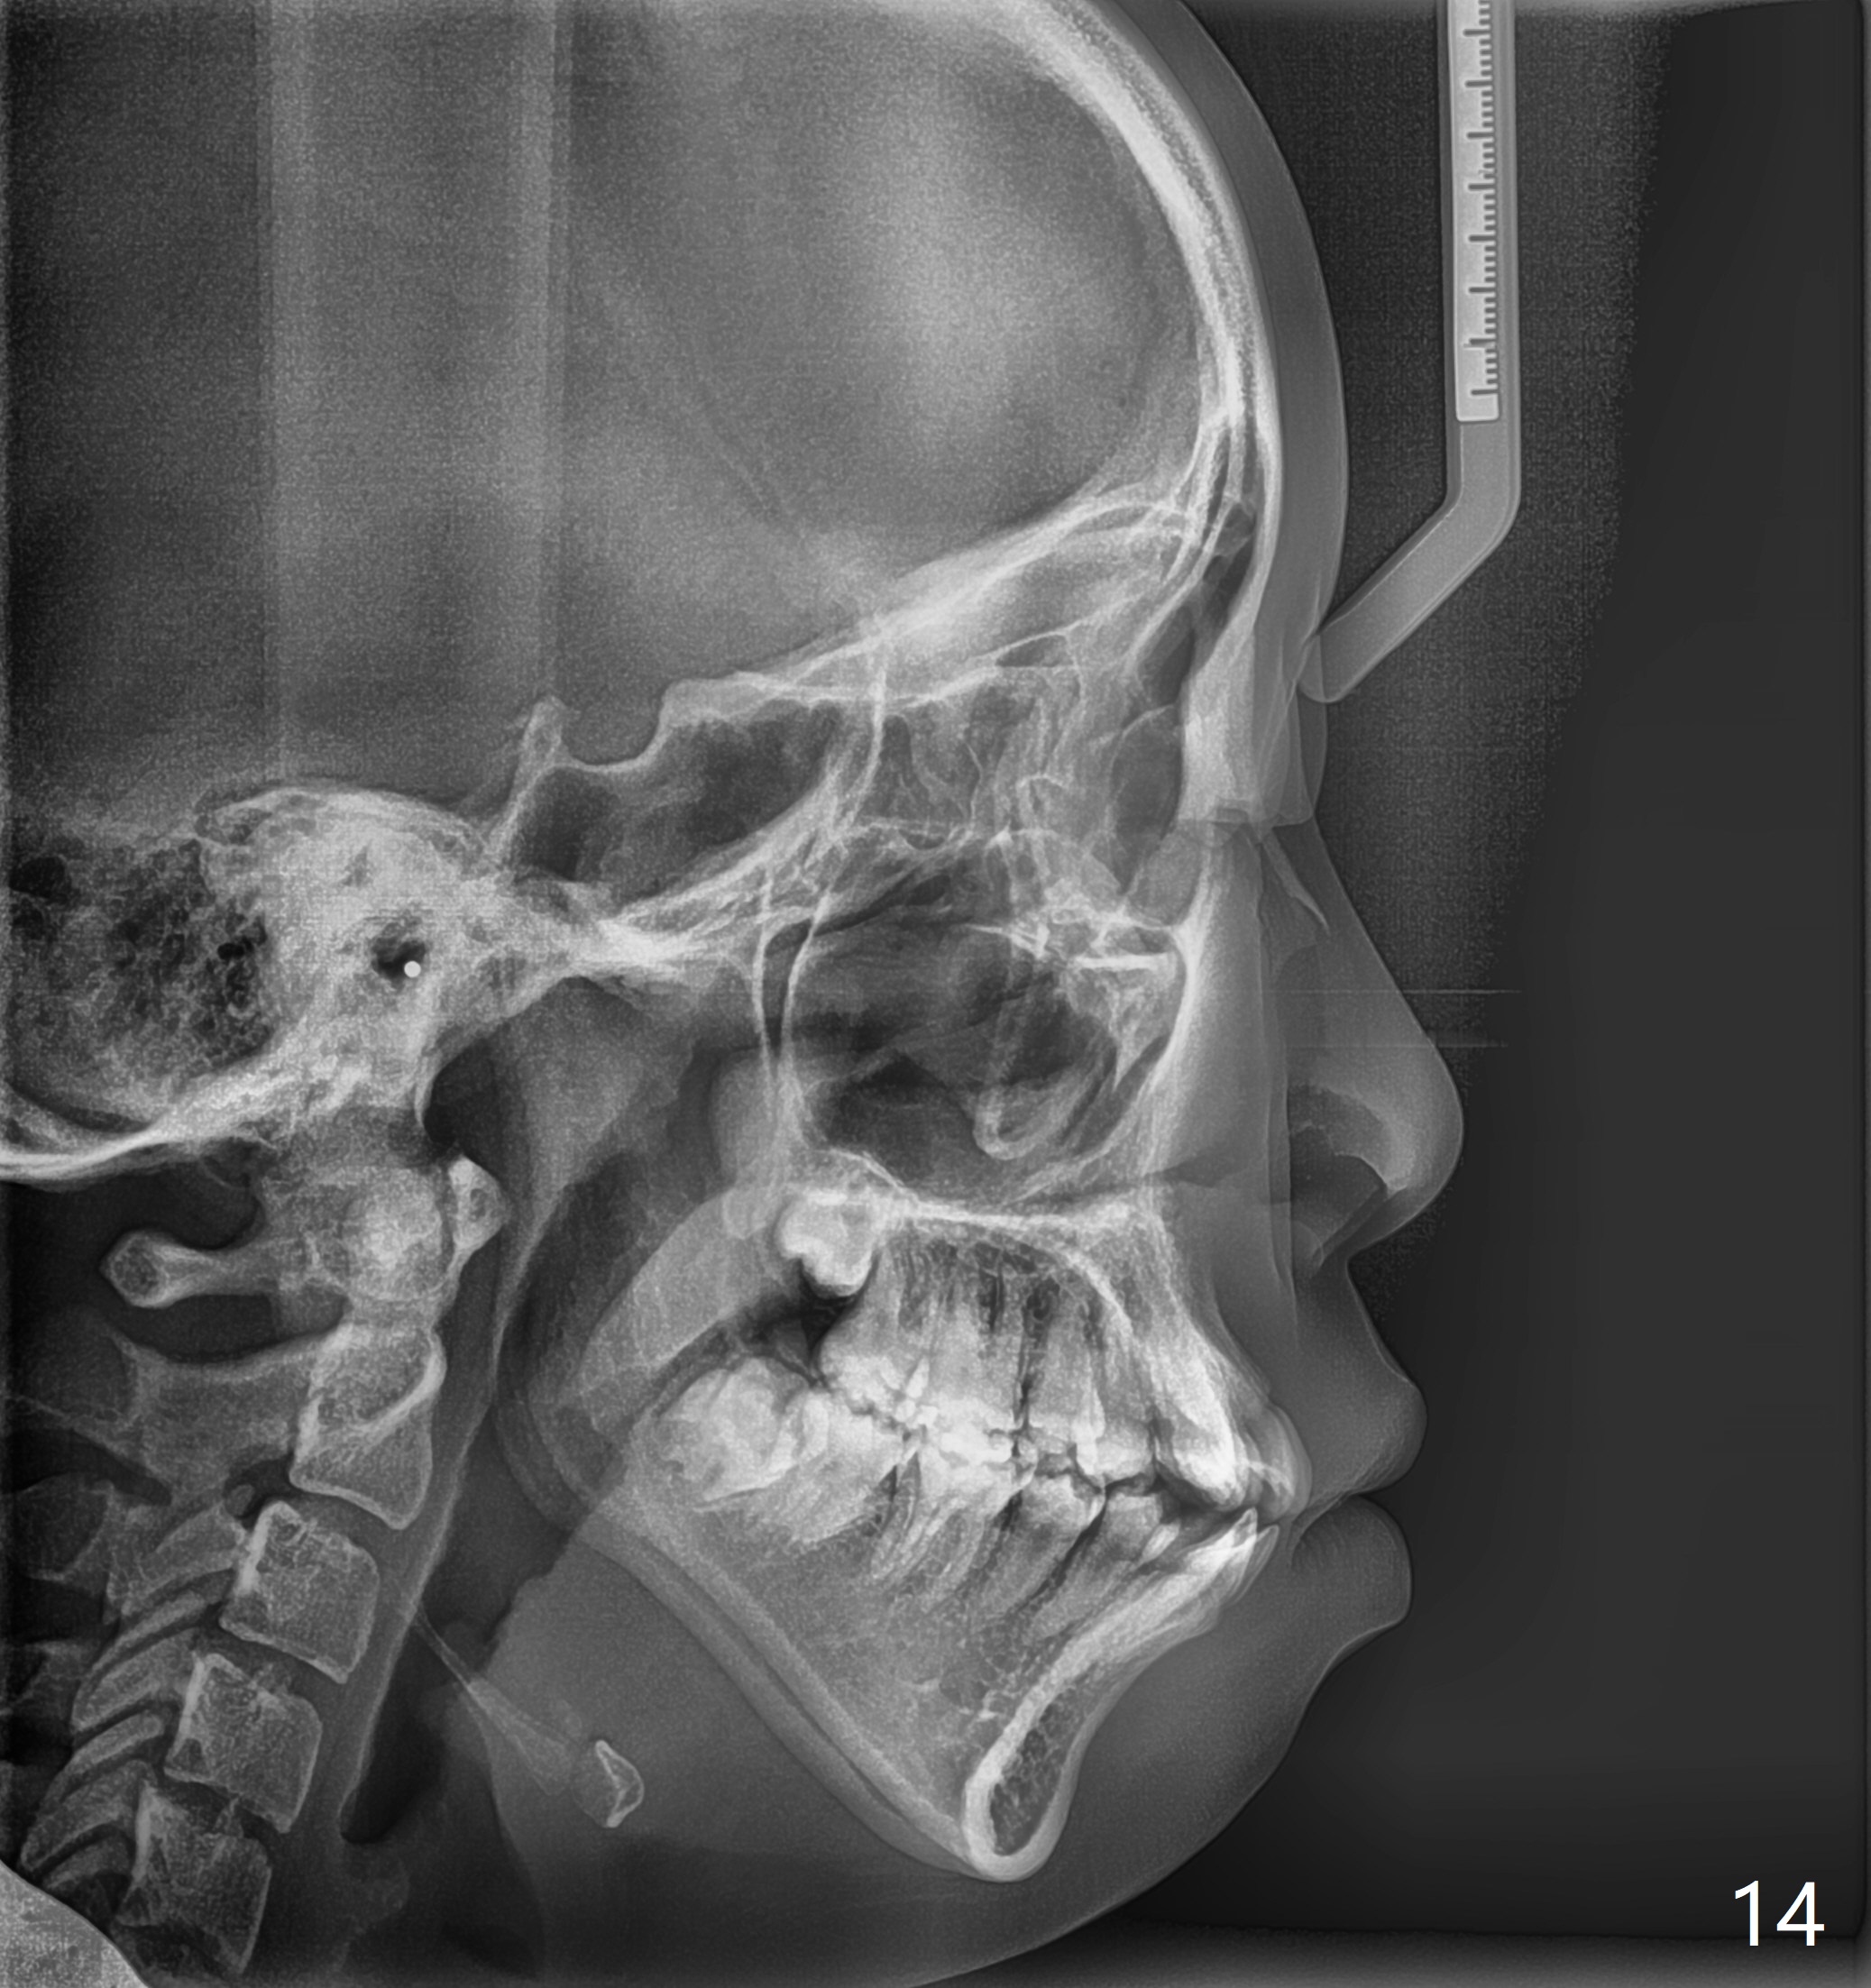

A 14-year-old woman has convex facial profile (Fig.1-4) with the upper midline shifted to the left (Fig.2). Since the roots of the 1st bicuspids are short (Fig.5), extraction should be easy. U3 will be retracted distal early with intention to correct the upper midline. With Class I occlusion at the canines and the 1st molars and good initial interdigitation (Fig.6-11), orthodontic treatment should be rewarding. Because of severe crowding (tight contact, Fig.12,13), place separators after extraction and place bands and brackets a few days later. Cephalometric analysis (Fig.14) shows that SNB is greater than SNA (82.4 vs. 81.8 degree); after extraction, retract the lower anterior teeth prior to the upper ones. It is easy to place separators after extraction (Fig.16,17).